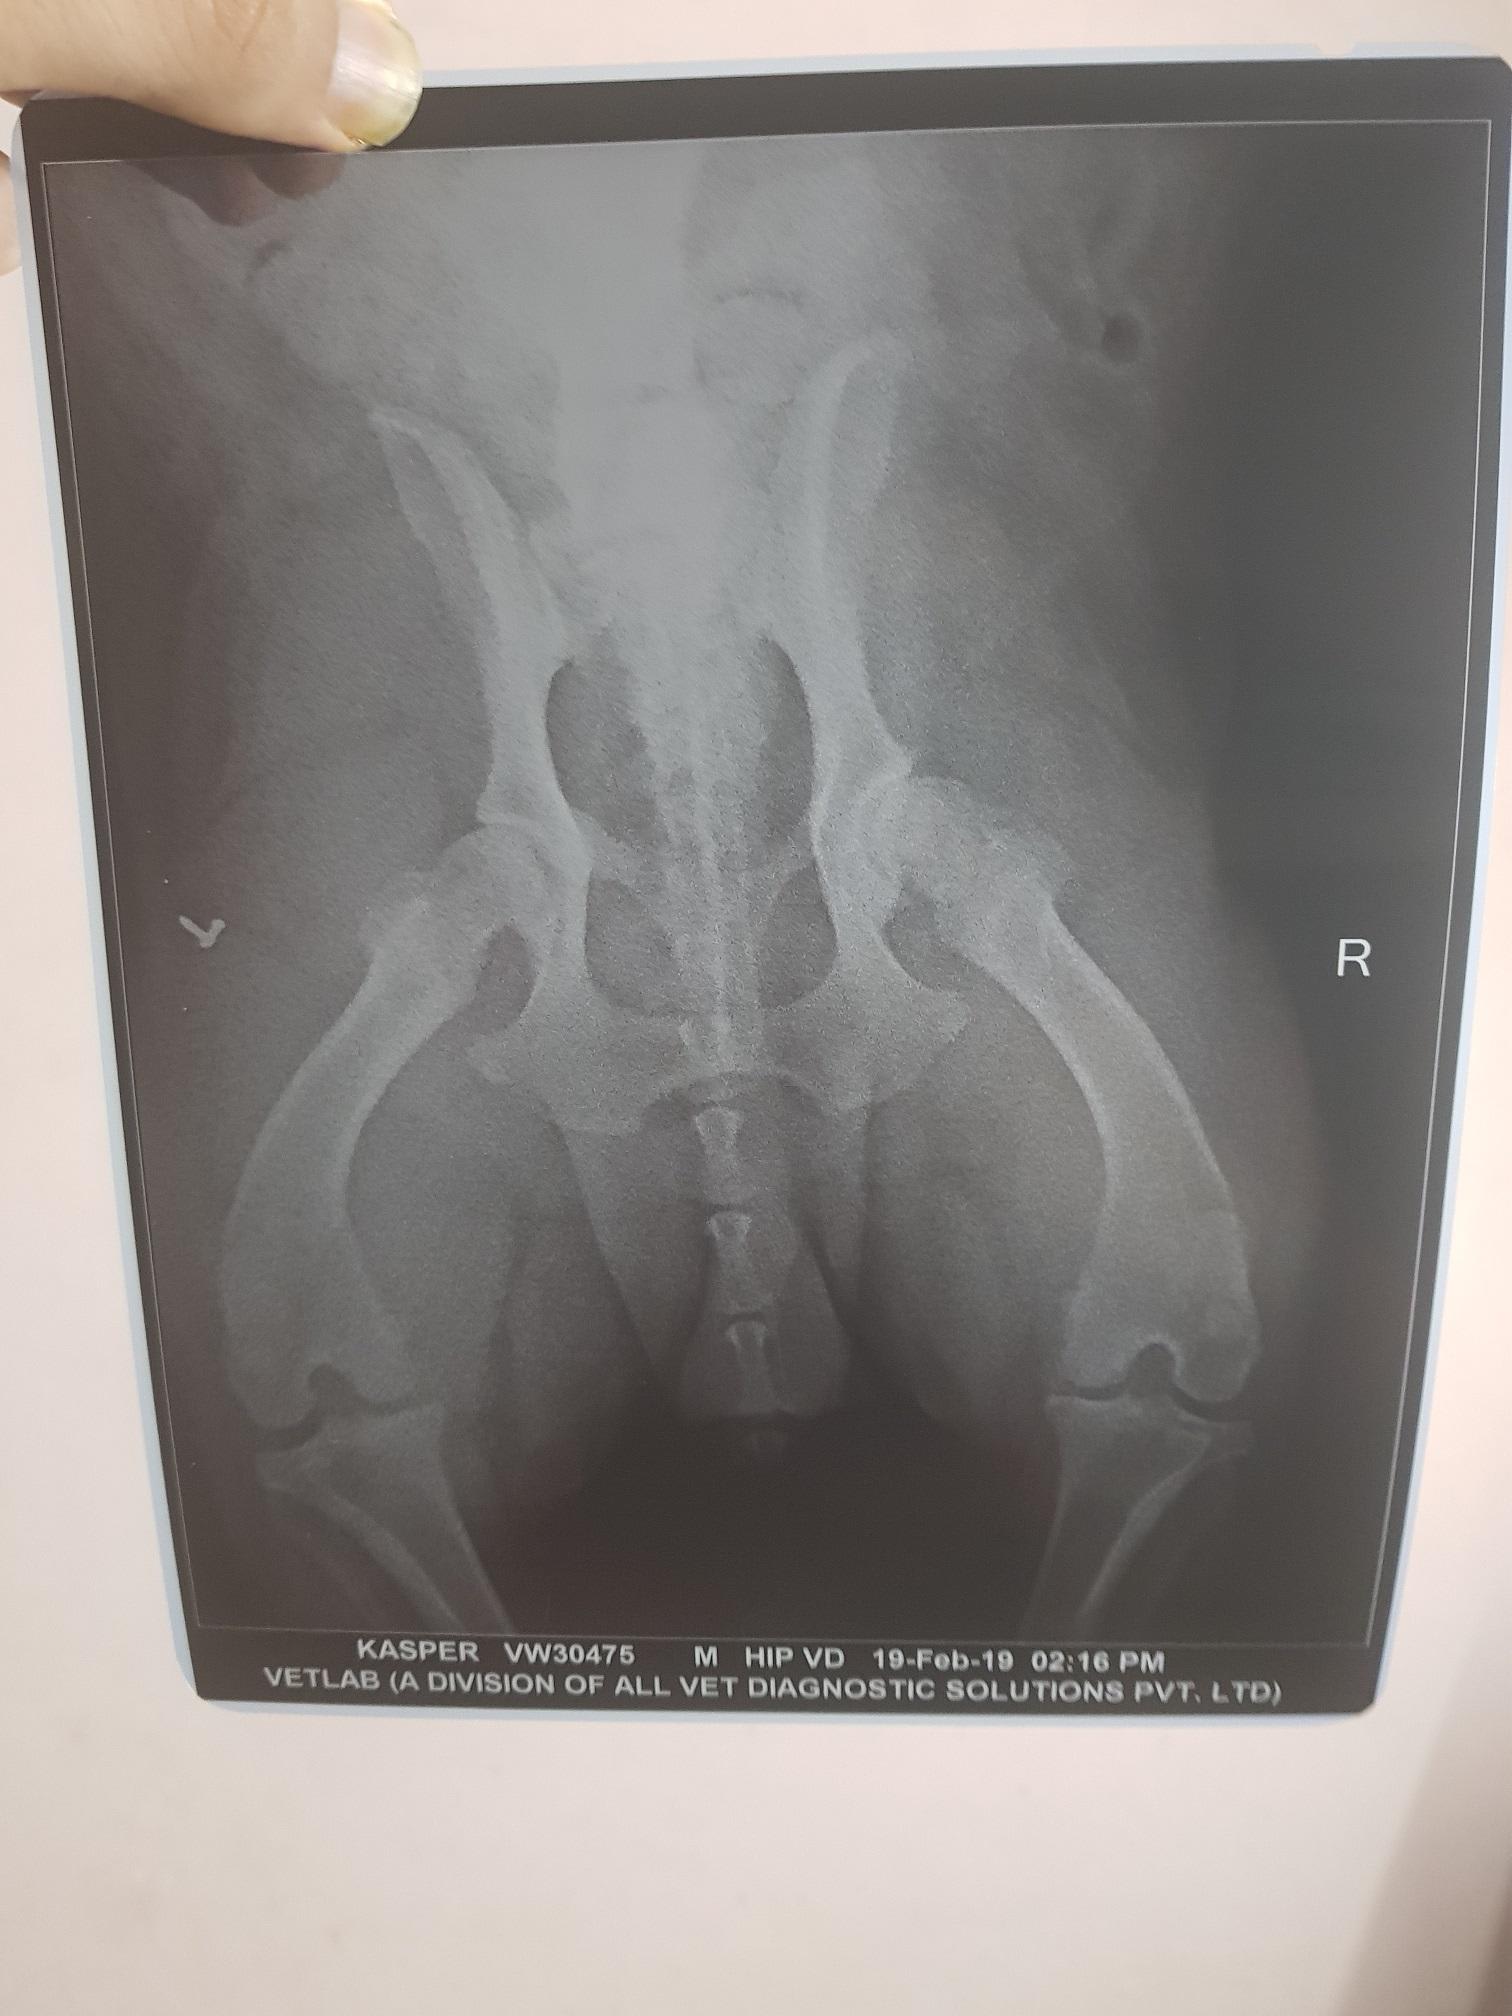

My rottweiler dog leg shaking. i am attaching the Xray report. kindly tell me what should i do ? please tell me the medicine for my pet :(

Hello. Kasper has evidence of hip dysplasia. It is not severe, but enough to cause your pet some discomfort. We routinely see these type of changes, especially in the larger breed dogs. Treatment includes the use of pain medications, joint supplements, weight loss, & consistent, but easy exercising. Pain meds include NSAIDs such as carprofen, Previcox, Deramax & Meloxicam, additional pain relief such as Tramadol &/or Gabapentin, & joint supplements such as glucosamine/chondroitin sulfate, Adequan injections & ocassionally omega 3 fatty acids. Thanks for using Petco Pet Education Center, formerly Petcoach.